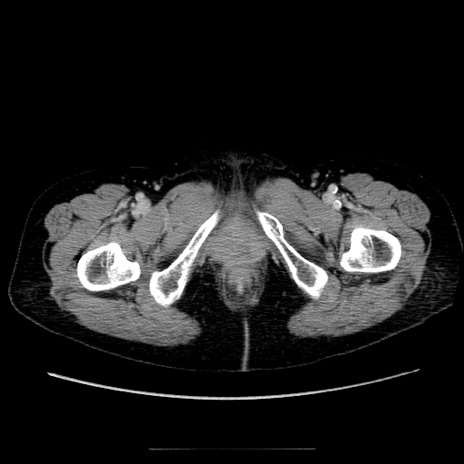

症例5(横断像)

【症例】70歳代女性

【主訴】お腹が張る

【現病歴】1週間くらい前から腹部膨満の自覚あり。昨日夜から増悪したため、本日救急外来受診。

【身体所見】意識清明、BT 36.5℃、BP 165/106mmHg、HR 80bpm、SpO2 98%、腹部:膨満、軟、自発痛・圧痛なし、触診にて不快感あり、腸蠕動音:減弱

【データ】WBC 12600、CRP 1.04